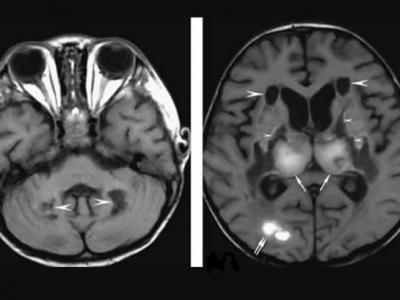

新冠肺炎患者现罕见并发症“急性坏死性脑

新冠肺炎患者现罕见并发症“急性坏死性脑病变” 精神错乱中风(蜘蛛网eeook.com报道...